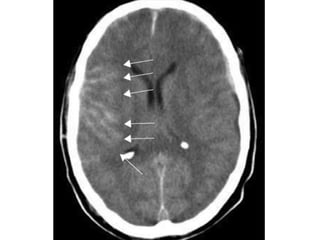

Multiple areas

of linear high

density are

seen within the

right cerebral

sulci

(arrows); these

represent

areas of acute

subarachnoid

haemorrhage

Multiple areas of linearhigh density are seen within the right cerebral sulci (arrows); these represent areas of acute subarachnoid haemorrhage